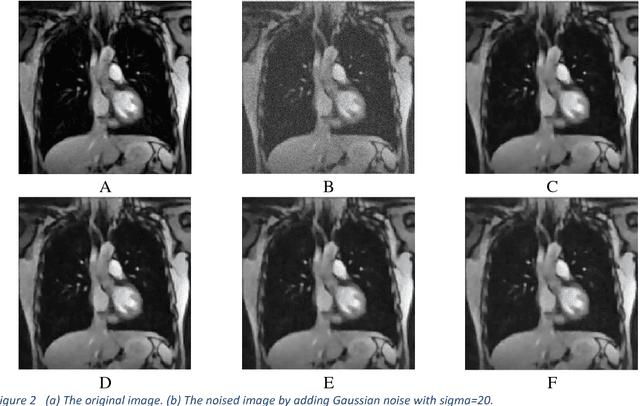

Recently, the problem of blind image separation has been widely investigated, especially the medical image denoise which is the main step in medical diag-nosis. Removing the noise without affecting relevant features of the image is the main goal. Sparse decomposition over redundant dictionaries become of the most used approaches to solve this problem. NMF codes naturally favor sparse, parts-based representations. In sparse representation, signals represented as a linear combination of a redundant dictionary atoms. In this paper, we propose an algorithm based on sparse representation over the redundant dictionary and Non-Negative Matrix Factorization (N-NMF). The algorithm initializes a dic-tionary based on training samples constructed from noised image, then it searches for the best representation for the source by using the approximate matching pursuit (AMP). The proposed N-NMF gives a better reconstruction of an image from denoised one. We have compared our numerical results with different image denoising techniques and we have found the performance of the proposed technique is promising. Keywords: Image denoising, sparse representation, dictionary learning, matching pursuit, non-negative matrix factorization.